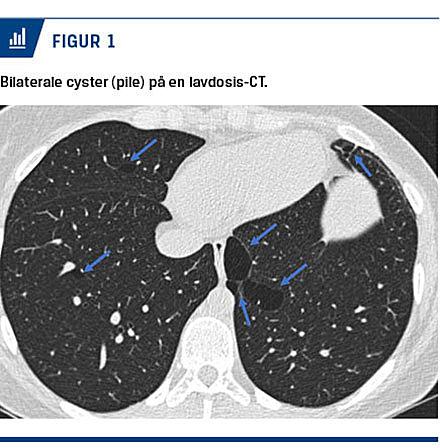

I forløbet blev der påvist normal lungefunktion ved dynamisk spirometri og mild anstrengelsesudløst laryngeal obstruktion ved laryngoskopi. En lavdosis-CT af lungerne to år efter den initiale HRCT viste cyster i alle områder af lungerne (Figur 1).